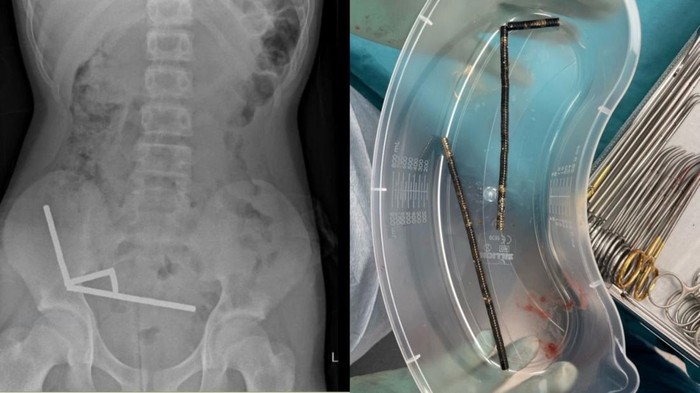

Dokter di Selandia Baru terpaksa mengeluarkan sebagian usus seorang remaja laki-laki berusia 13 tahun. Ini terjadi setelah remaja itu menelan puluhan magnet kuat yang dibeli di toko daring.

Remaja tersebut menelan hingga 100 magnet kecil berdaya tinggi yang dipesannya itu. Para ahli bedah menyebut kasus ini cukup mengkhawatirkan, karena kemudahan anak-anak untuk mendapatkan produk tersebut.

"Ia mengungkapkan telah menelan sekitar 80-100 magnet neodymium berdaya tinggi, berukuran 5x2 mm sekitar satu minggu sebelumnya, yang dibeli dari pasar daring luar negeri," sambungnya.